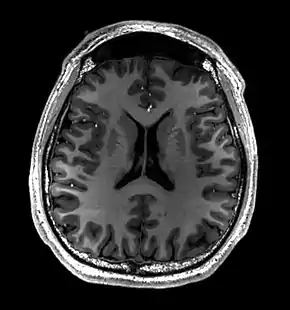

Brain regions on T1 MRI

T1 (note CSF is dark) with contrast (arrow pointing to meningioma of the falx)